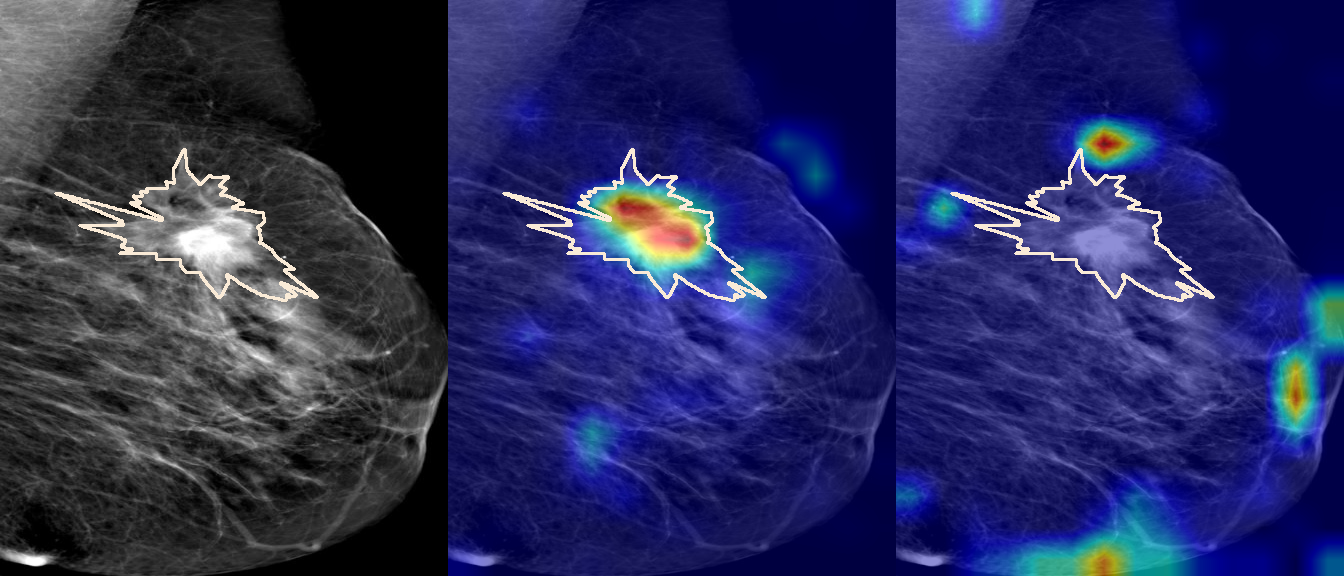

To interpret the decision-making process behind the quantitative results, we visualized Class Activation Maps (CAM) for the top-performing methods, ERM and VREx. Figures 1 through 2 illustrate discriminative regions identified by the models within the full mammograms.

Localization of Clinical Features: A key concern in medical AI is whether high performance stems from genuine pathology detection or spurious background correlations. Our visualizations suggest that Standard ERM achieves its superior quantitative performance by predominantly prioritizing clinical cues. As shown in the top rows of the Figure 1 and Figure 2, the ERM-trained models consistently focus attention on the specific lesion regions within the breast tissue. This demonstrates that despite lacking explicit invariance constraints, ERM is capable of learning robust, medically relevant features when trained on diverse multi-source data.

Attention Drift in Both Methods: While both ERM and VREx generally identify the correct region of interest in successful cases, neither method is immune to attention drift. We observe instances in both training paradigms where the model focuses on irrelevant areas, such as healthy fibroglandular tissue or background artifacts (e.g., rows 5 and 6 in Figure 1). This indicates that while VREx is designed to penalize instability, it does not guarantee perfect anatomical focus compared to the unconstrained ERM baseline.